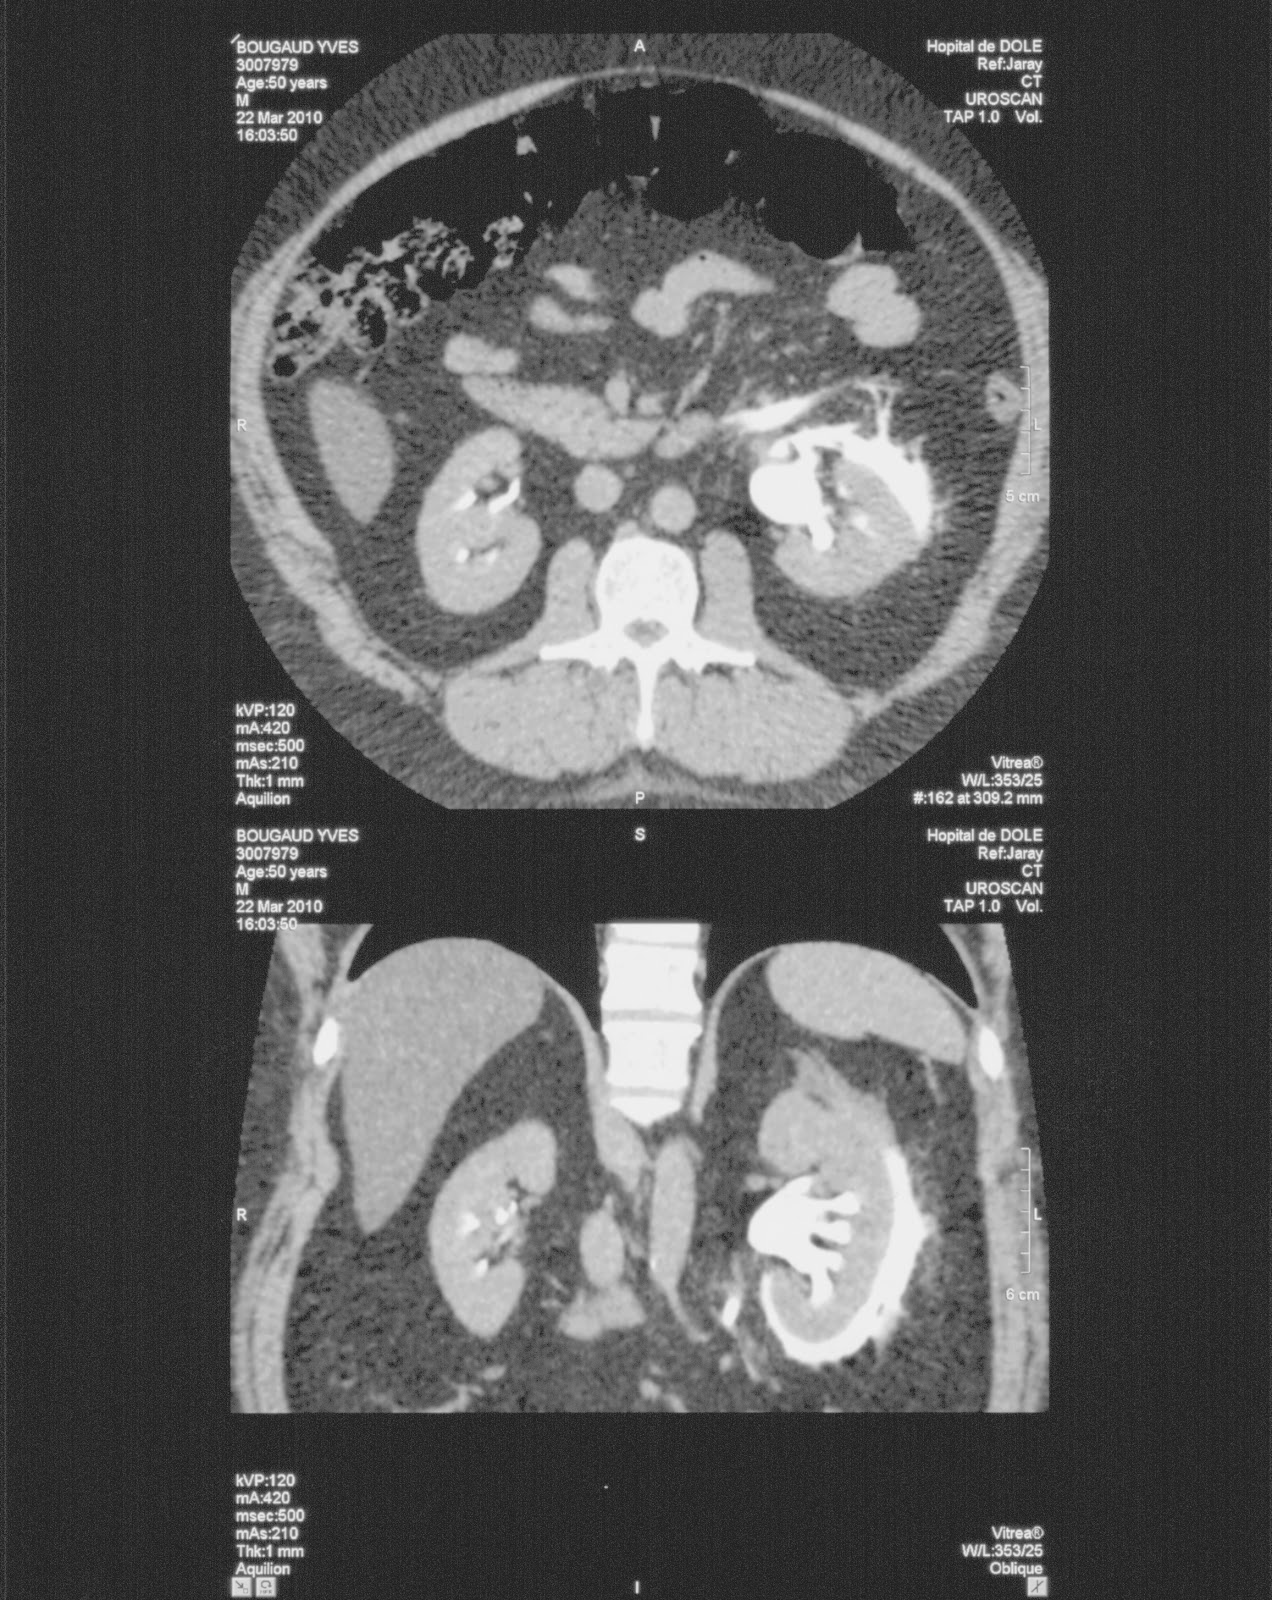

contrast extravasation from the renal pelvis to the perirenal space in the late phase

- Forniceal rupture